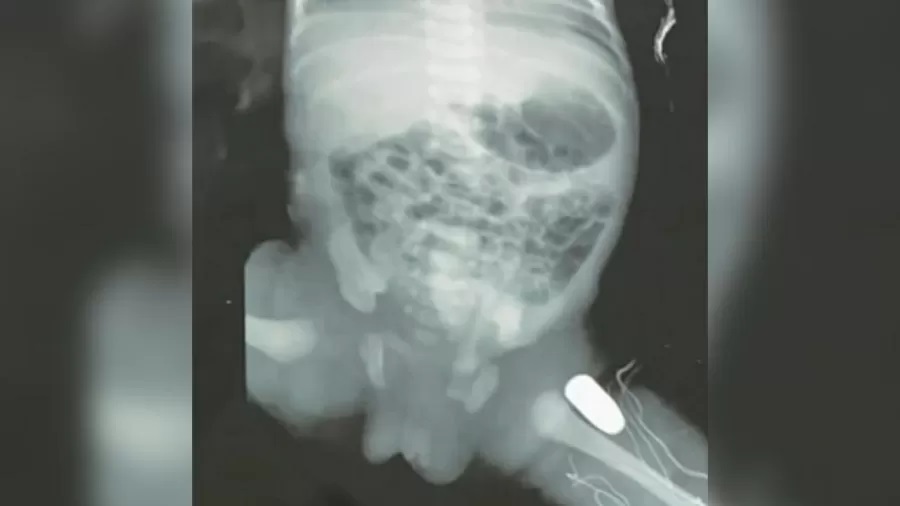

Uma adolescente de 15 anos passou por um parto de emergência após ser baleada na barriga em Imperatriz (MA). A bala ficou alojada na perna da bebê.

A garota, grávida de 33 semanas, foi baleada na noite do domingo (16). Ela foi levada ao Hospital Materno Infantil de Imperatriz. Autoridades não informaram as circunstâncias na qual a garota foi baleada.

Recém-nascida deve passar por cirurgia nesta segunda-feira (17). Não há detalhes sobre a extensão do ferimento na criança. Ao UOL, um parente da adolescente informou que as duas passam bem.